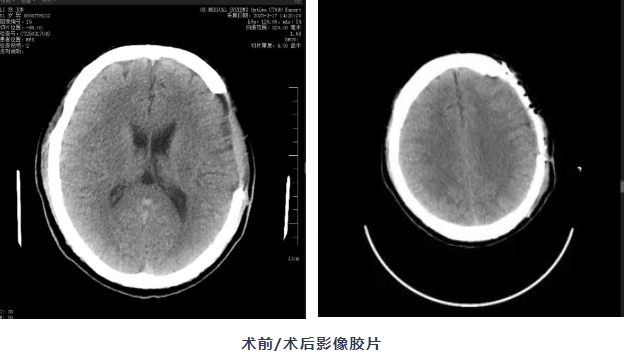

在手麻科、放射科等多学科配合下,邱斌主任团队凭借丰富的颅脑手术经验,像拼乐高积木一样,精准将这个乳白色的"头骨拼图"嵌入缺损部位,术中出血少、操作时间短,颅骨外形自然对称。

“看着镜子里的自己,终于敢正视伤疤了。”术后第二天,张师傅摸着自己平整的头部,感觉重新找回了久违的“安全感”。现在,他敢摘下帽子散步,头痛头晕症状也明显减轻了。

这是我院首例PEEK颅骨修补术,标志着医院在颅脑创伤修复领域实现了技术新突破,为复杂颅骨缺损患者提供了更精准、更安全的治疗方案。如果您或家人有头部外伤,或手术后的颅骨缺损,长期头痛、头晕、怕震动,因头部凹陷产生心理障碍,欢迎咨询我院神经外科,电话:029-87865309,我们用温暖科技,帮您重塑完整人生!